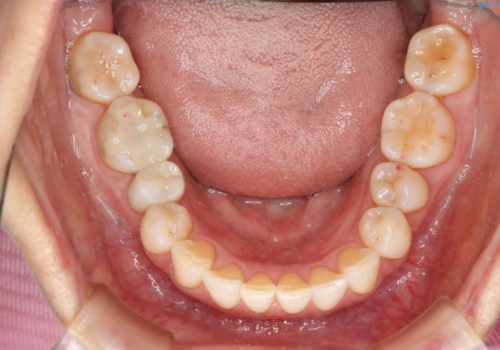

前歯の反対咬合、奥に引っ込んでしまっている歯をインビザラインで治療する

上の前歯の反対咬合があり、治療の途中で下の前歯を乗り越える必要があります。

インビザラインでこのような症例を行う場合、乗り越えるのに必要な期間が長くなります。

その為、奥歯で咬みにくい期間が長くなってしまいやすいです。